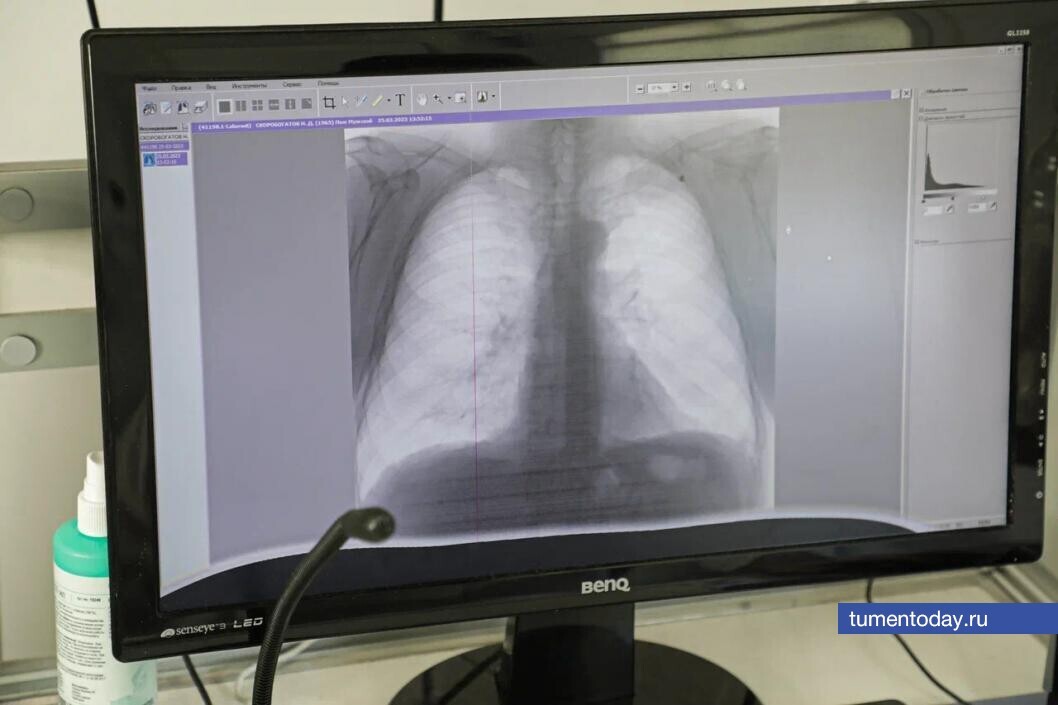

Специалисты тюменского многопрофильного клинического медицинского центра «Медицинский город» помогают землякам бороться с онкологическими заболеваниями. Как отмечают эксперты, многие из этих недугов можно предотвратить, если избегать основных факторов риска возникновения рака.

Среди основных врачи называют табакокурение. Оно может привести не только к раку легких, но и к опухолям в области рта, гортани, поджелудочной железы и других органов.